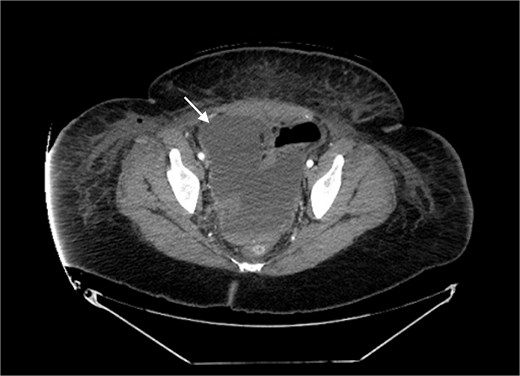

A 41 year old female presented to the emergency department with clinical presentation of peritonitis 4 days after a robot-assisted laparoscopic cholecystectomy, hiatal hernia repair, and gastric sleeve converted to Roux-en-Y gastric bypass. The patient underwent a diagnostic laparoscopy and was found to have a necrotic Roux limb in the setting of venous congestion. The Roux limb along with the necrotic congested mesentery was resected, and the Roux-en-Y gastric bypass was recreated. Postoperatively, the patient developed fevers and tachycardia despite receiving broad-spectrum antibiotics. Labwork showed leukocytosis to 16.1 with left shift to 81.5%. Computed tomography (CT) scan showed a saddle pulmonary embolism and pelvic fluid collection measuring 14.2 × 7.5 cm (Figs 1 and 2). The patient was started on therapeutic anticoagulation, and interventional radiology (IR) was consulted. No thrombectomy was indicated as there were no signs of right heart strain, however IR placed a 8.5 French drainage catheter in the abscess cavity. Wound cultures grew Enterococcus faecalis Group D and Proteus mirabilis.

Pelvic fluid collection prior to IR drainage measuring 15.4 × 10.6 cm, in the axial view.

Pelvic fluid collection prior to IR drainage measuring 15.4 × 10.6 cm, in the coronal view.